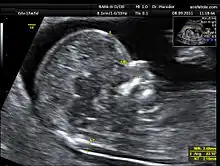

Clarté nucale

La clarté nucale, petite zone anéchogène (ne renvoyant pas d'écho en échographie) située sur le crâne d'un fœtus humain pendant le premier trimestre de grossesse, permet de dépister certaines anomalies congénitales, en particulier la trisomie 21.

La clarté nucale, comme son nom l’indique, se situe au niveau de la nuque du fœtus. Elle est due à un petit décollement entre la peau et le rachis et correspond à une zone dite anéchogène (c’est-à-dire qui ne renvoie pas d’écho lors de l’examen). Tous les fœtus présentent une clarté nucale au cours du premier trimestre, mais cette clarté disparaît ensuite.